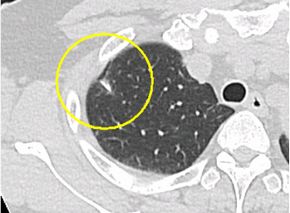

肺がん・縦隔腫瘍に対する低侵襲治療

従来の肺癌の手術は20cm前後の皮膚切開で肋骨、筋肉を切断し、肋間を開胸器で開

大しなければなりませんでした(開胸手術)。当院では内視鏡を用いた手術(胸腔鏡手術)

を行っており、従来の手術法と比べて傷が小さく筋肉や肋骨を切断しないため、術後の

痛みや機能の悪化が少ないと考えられています。当院では高度の進行病変などを除いて

は、ほぼ全例に胸腔鏡を用いた手術を行っております。

当院における早期肺がんに対する診療と治療の流れ

早期肺がんの患者さんには、全例で低侵襲な胸腔鏡下手術を行っています。また早期肺

がんに対する肺ラジオ波治療も積極的に行っています。一方、進行肺がん(大きい腫瘍、